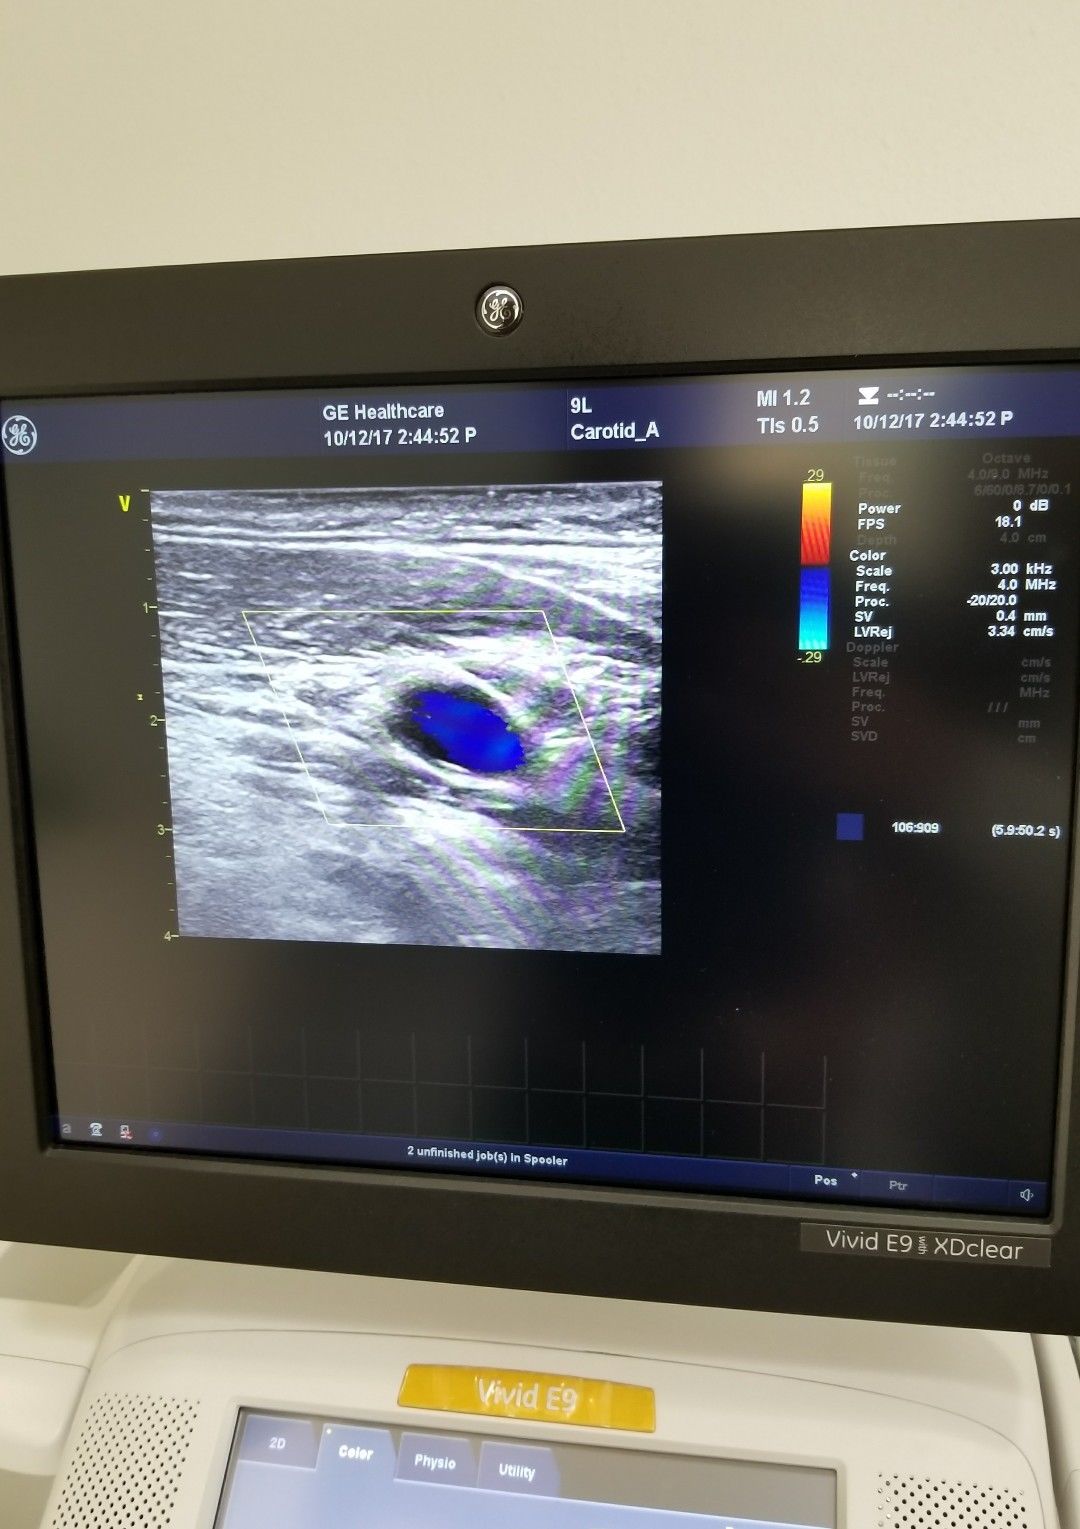

Brand: GE

Model: 9L-D